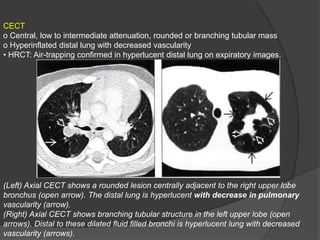

CECT

o Central, low to intermediate attenuation, rounded or branching tubular mass

o Hyperinflated distal lung with decreased vascularity

• HRCT: Air-trapping confirmed in hyperlucent distal lung on expiratory images.

(Left) Axial CECT shows a rounded lesion centrally adjacent to the right upper lobe

bronchus (open arrow). The distal lung is hyperlucent with decrease in pulmonary

vascularity (arrow).

(Right) Axial CECT shows branching tubular structure in the left upper lobe (open

arrows). Distal to these dilated fluid filled bronchi is hyperlucent lung with decreased

vascularity (arrows).